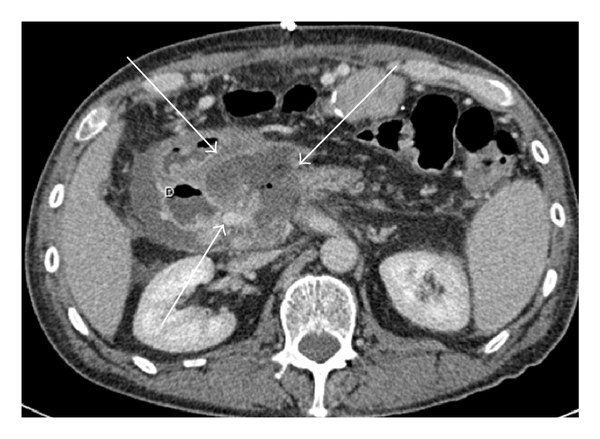

As Figures 1–5 demonstrate, the immediate postablation bed and zone are invariably larger than the original ablated tumor. We remain descriptive because the entire bed was extremely difficult to measure owing to the amorphous, irregular nature of the ablation. Moreover, the ablated tissue is not within an encapsulated organ; therefore, the ablation zone does not have defined borders as seen after, for instance, liver ablation. Four patients that showed continued stable disease are highlighted in Figures 1 through 4. An amorphous, hypoattenuating region with irregular shape persisted in subsequent CT scans in all patients with “stable disease.” Moreover, the ablation zone was typically smaller (due to decreased edema, hyperemia, and granulation tissue) than the immediate postablation bed in the following months and remained stable provided there was no recurrence. Imaging findings demonstrating recurrence are shown in Figure 5. Along with persistent irregular shape the ablation zone showed increased tumor bulk and extension as well as new mass effect (new narrowing of a blood vessel). Enhancement of the ablative bed was variable and often showed increased enhancement in the three-month and longer follow-up images. This was felt to be related to development of granulation tissue and fibrosis.

In our study, we found that the postablation bed is larger in volume than the initial mass. This is expected because it contains the tumor and the ablative margin. The postablation bed and zone appear irregular, amorphous, and hazy without margins or true boundaries. The ablation zone may decrease in size from the initial post-op bed to the initial surveillance study as the surrounding edema/fluid and inflammation resolve revealing the true ablation zone; however, as mentioned above, since there have been reports of an ongoing apoptotic process that persists up to 6–8 weeks after ablation, it will not be unusual to see some increase in volume in surveillance [19, 20]. Therefore, size is considered secondary in the CT evaluation for this reason and because the postablative bed/zone has poorly defined margins, making objective imaging assessment (size, attenuation) cumbersome. This may undoubtedly affect the accuracy and reproducibility of the measurement. Nonetheless, any increase in volume after stabilization of the postablation zone is considered worrisome for recurrence (Figure 5).

Other clues that may suggest recurrence are any new encasement or narrowing of adjacent vessels or any subjective extension of soft tissue outside the boundaries of the previously established baseline ablation zone. However, in patients that have undergone prior radiation therapy or undergo post-IRE radiation therapy, persistent isolated narrowing (without other worrisome findings) is not always recurrence and must be followed with serial imaging, clinical evaluation, and CA19-9 serum tumor markers. Vessels within and adjacent to the ablation bed may show narrowing immediately after the procedure, but this should resolve or at least remain stable in subsequent studies. Often, if narrowing of a vessel is seen with the index tumor it will often persist after ablation. For equivocal cases, PET/CT may play a role in differentiating postablative changes from recurrence [25].